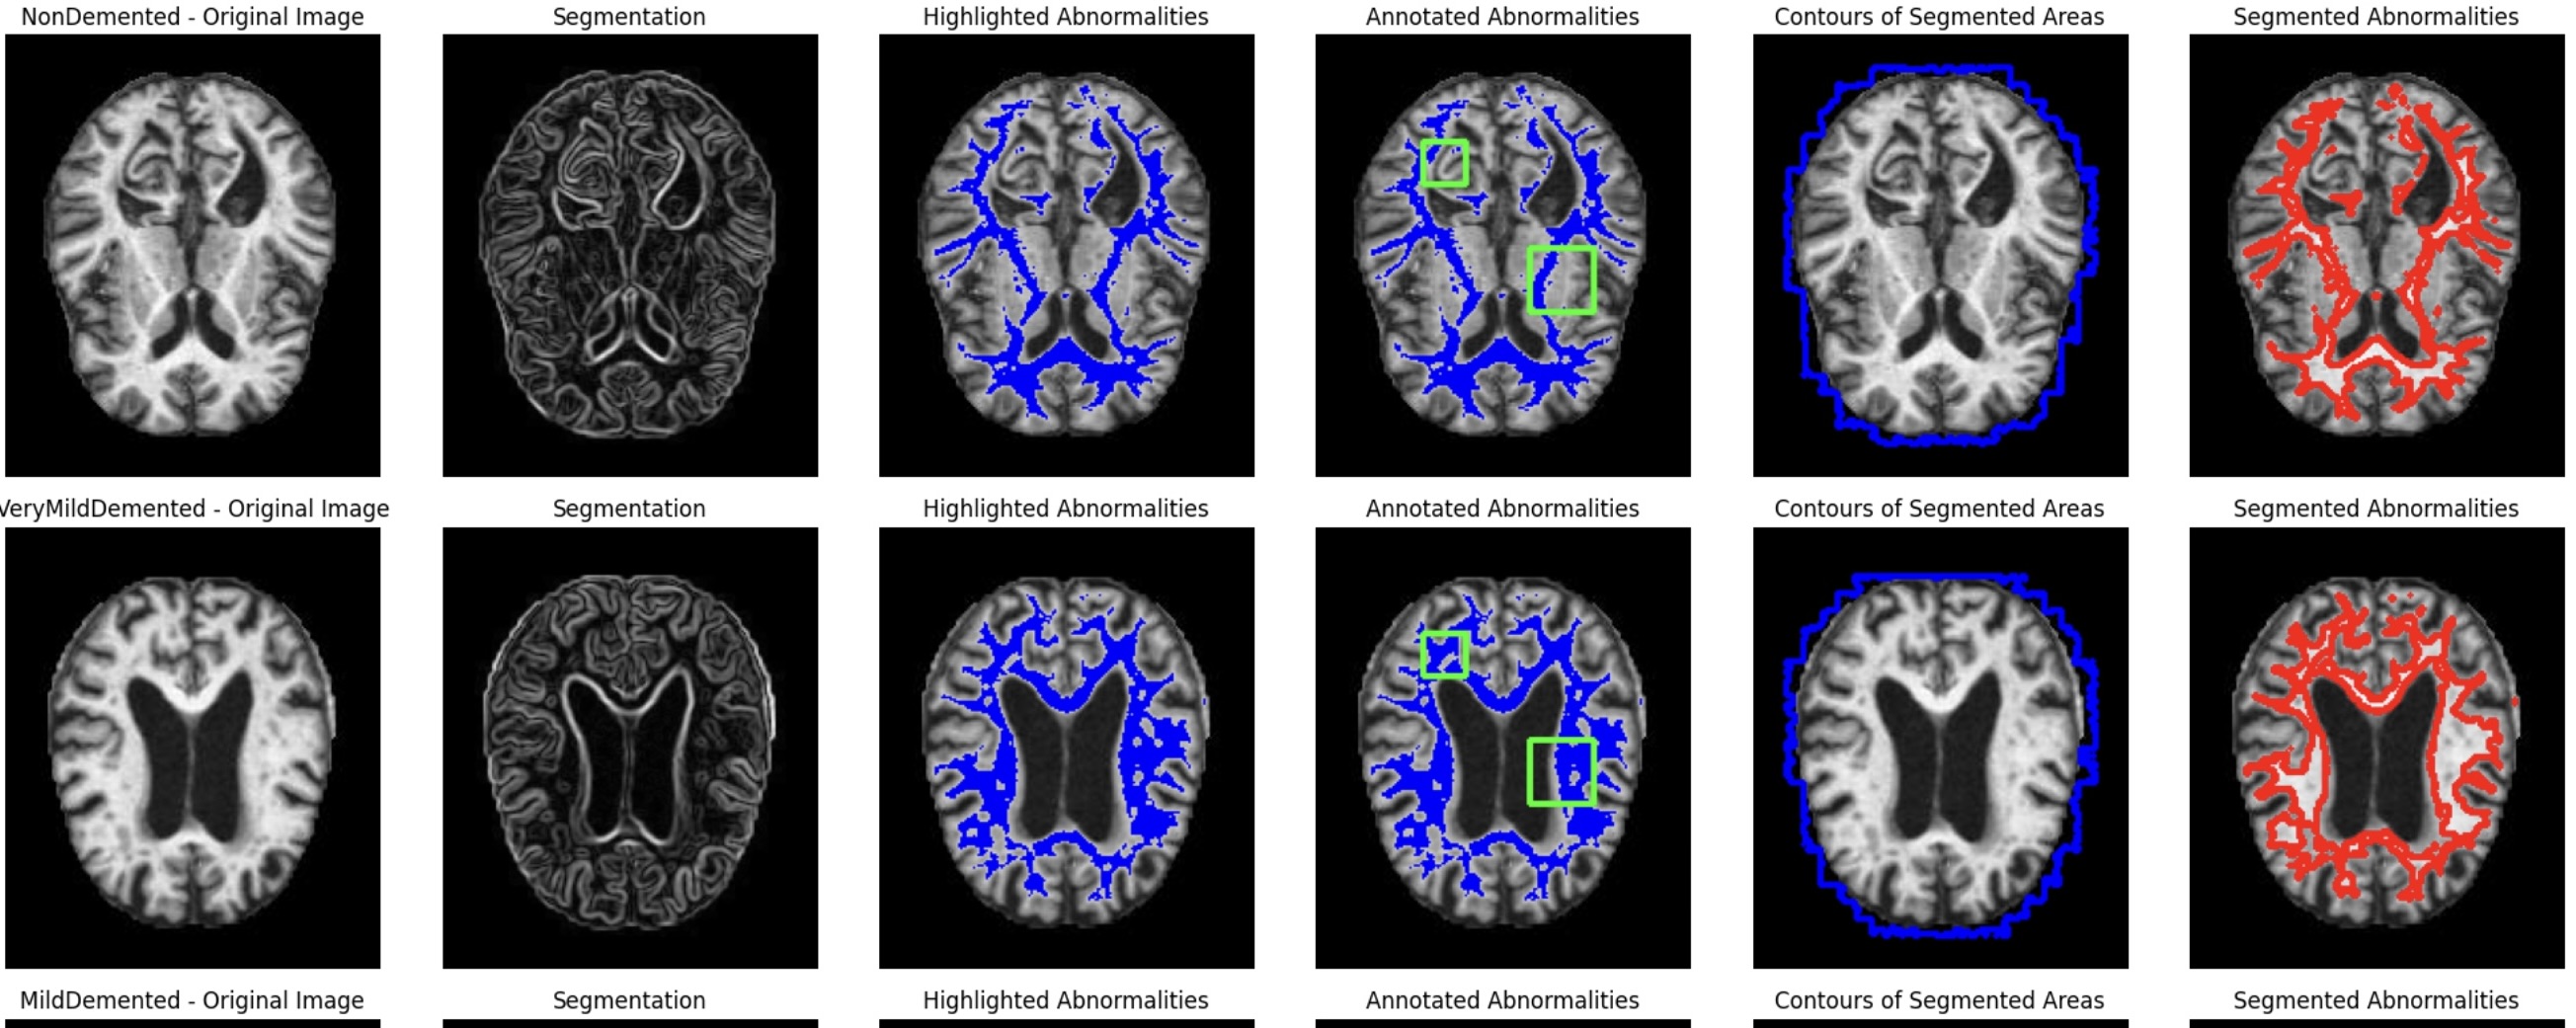

Alzheimer's Disease Detection and Prediction

The image shows a collection of MRI brain scans labeled with different stages of dementia: "VeryMildDemented," "NonDemented," and "MildDemented." These scans are typically used to observe the structure of the brain and to detect changes associated with cognitive decline or dementia. The scans labeled "NonDemented" show a normal brain structure with clear, defined shapes of the brain's ventricles and surrounding tissue, indicating no visible signs of dementia-related damage. The "VeryMildDemented" and "MildDemented" scans may display slight differences in the ventricle size or other subtle changes, which could be indicative of the early stages of dementia.